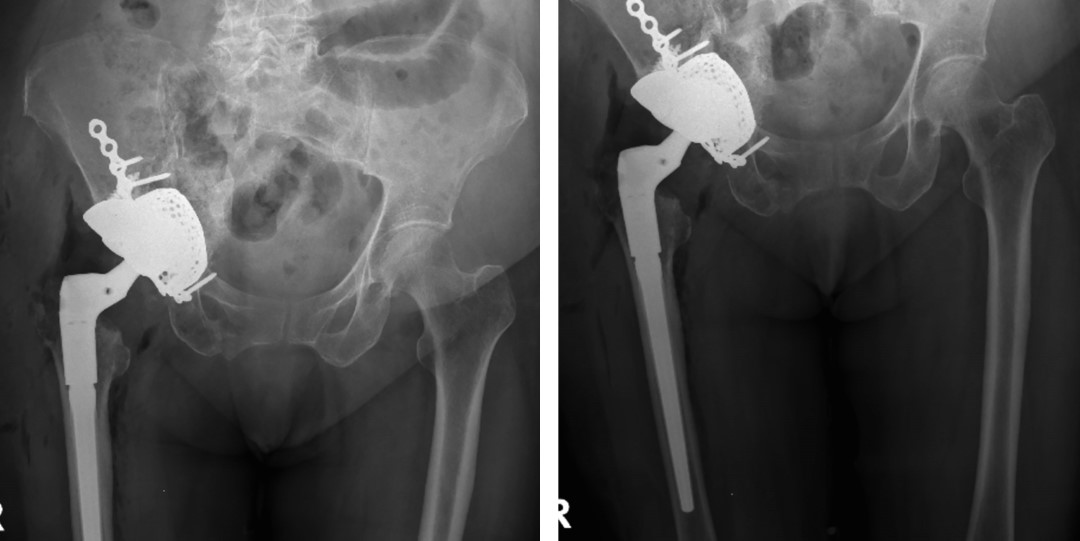

Se realiza reducción de componentes protésicos y verificación de adecuada estabilidad. Síntesis de diéresis y control radiográfico postquirúrgico (Figura 6).

Figura 4

Figura 5

Figura 6